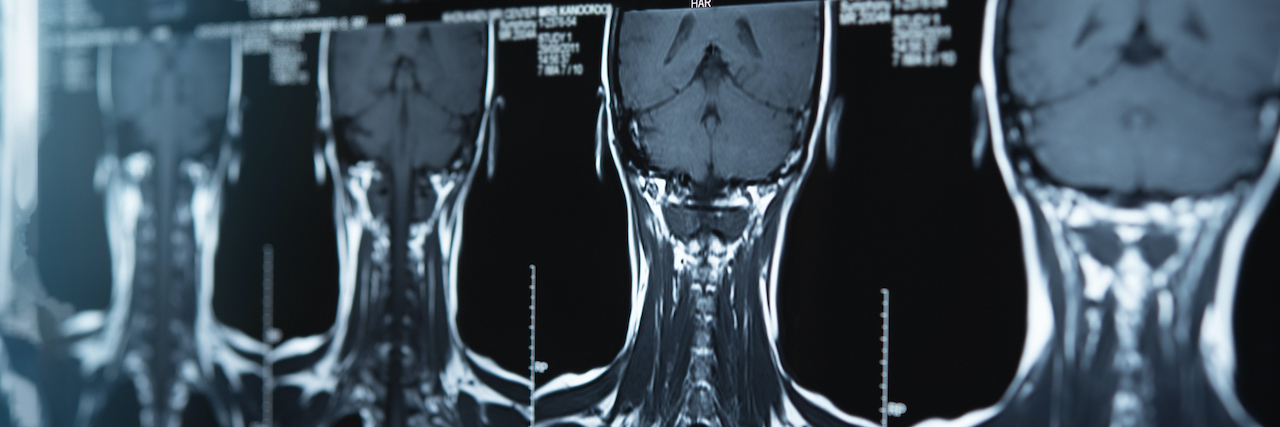

When we arrive we start with X-rays which only take a few moments because we are now pros. We wait to be called back to a room where we see a nurse, a PA and the doctor separately in that order. Sometimes a medical student or a resident tags along as well. The PA pulls up the X-rays on the computer screen, opens up the measuring tool and clicks in rapid fire while plotting points on the photo of their spines.

We all hold our breath and think, “Does it look the same as the X-rays taken six months previous? It looks a little worse, but how much worse?”

The doctor arrives with smiles and handshakes for everyone (pre-COVID, of course). He settles into his seat and begins clicking furiously as he adjusts the measuring tool. Our anxiety surges. He announces the verdict.

My younger son’s curve is still very mild, less than 10 degrees. My older son’s is over 30 degrees as before but not much worse. Only a few degrees worse.